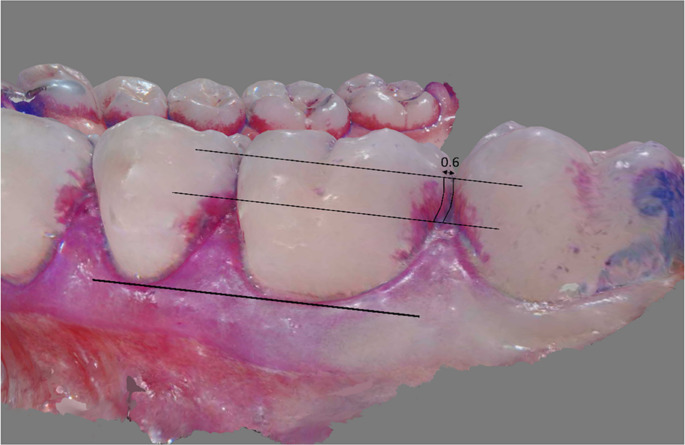

Materials and methods: A total of 37 adults (23.1 ± 3.2 years) participated. After habitual toothbrushing, plaque was disclosed and an intraoral scan was performed; afterwards, habitual flossing was videotaped, followed by a second intraoral scan of disclosed plaque. Participants then watched an instruction video. After one week of practice, flossing was again videotaped and intraoral scans were taken before and after flossing. On defined regions on images obtained from the four scans, plaque coverage was assessed with a three-level score (0: none, 1: <50%, 3: ≥50%). Proximal Surface Plaque Index (PSPI) was calculated as mean from all scores. A flossing performance score (FPS) was generated from the percentage of interdental spaces that were correctly flossed (interdental space reached, floss correctly applied and vertical movements; 0: totally imperfect, 3: perfect flossing). Ramfjord teeth (16, 21, 24, 36, 41, 44) were analysed, values are given as median [95% CI].